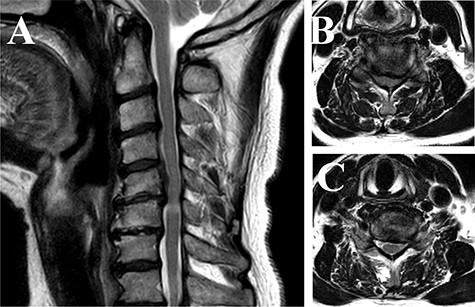

A 66-year-old Japanese male complained of weakness in his left fingers and hand, with neither gait impairment nor any symptoms in the lower extremities 1 year ago. Compressive lesions in the cervical spine were located at the C5-C7 level (Fig. 1), leading to the diagnosis as distal-type cervical spondylotic amyotrophy (CSA). Although the manual muscle test (MMT) of his left hand was grade 2, he preferred conservative therapy as his right hand was dominant.

Magnetic resonance imaging of the cervical spine (T2-weighted image). (A) Sagittal view images showed that compressive lesions in the cervical spine were located at the C5-C6 levels. The high signal lesion in the spinal cord was seen at the C5-C6 level. (B) Axial view of the C5-C6 level showed the spinal cord compression in the canal. (C) Axial view of the C6-C7 level showed the stenosis of the left side of foramen.